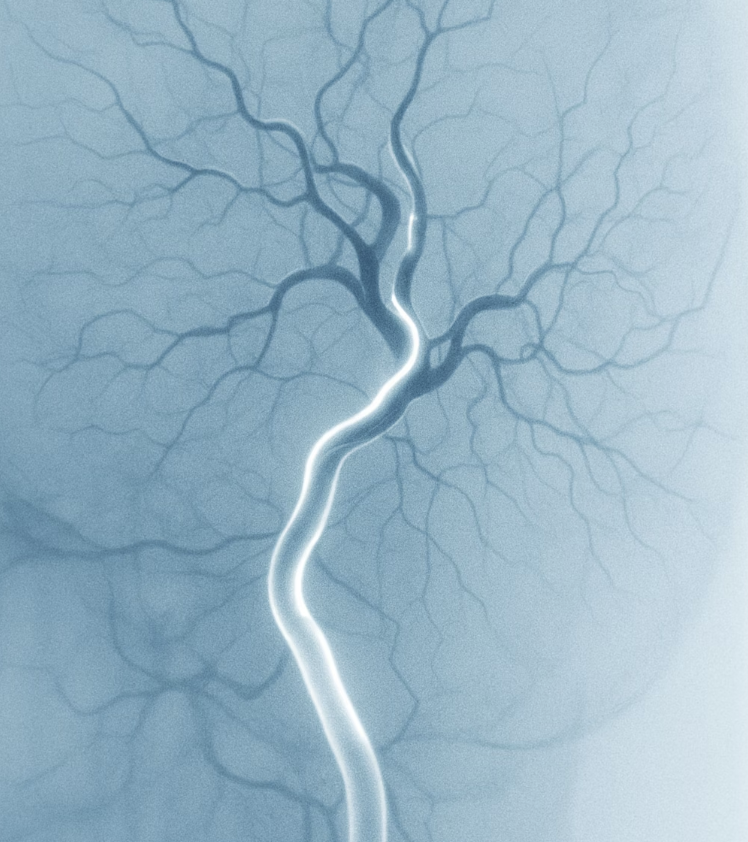

심장 혈관은 일반적인 엑스레이(X-ray) 촬영으로는 보이지 않습니다. 뼈와 달리 연한 조직이기 때문이죠. 그래서 의사들은 혈관의 길을 눈으로 볼 수 있도록 특별한 방법을 사용합니다. 바로 ‘조영제’라는 특수한 약물을 혈관 안으로 직접 주입하는 것입니다.

이 조영제는 엑스레이에 아주 선명하게 보이는 특성이 있습니다. 마치 투명한 호스 안에 검은색 잉크를 흘려보내면 호스의 모양과 막힌 부분이 뚜렷하게 보이는 것과 같은 원리죠. 이 조영제가 심장 혈관을 따라 흐르는 모습을 연속적으로 엑스레이 촬영하면, 우리는 혈관이 어디서 얼마나 좁아졌는지, 혈액이 잘 흐르고 있는지 마치 지도를 보듯 한눈에 파악할 수 있게 됩니다.